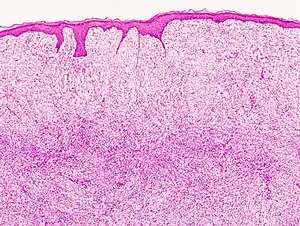

![]() | |

| Histopathological image of dermatofibrosarcoma protuberans. Local recurrence long after the first excision. H&E stain | |